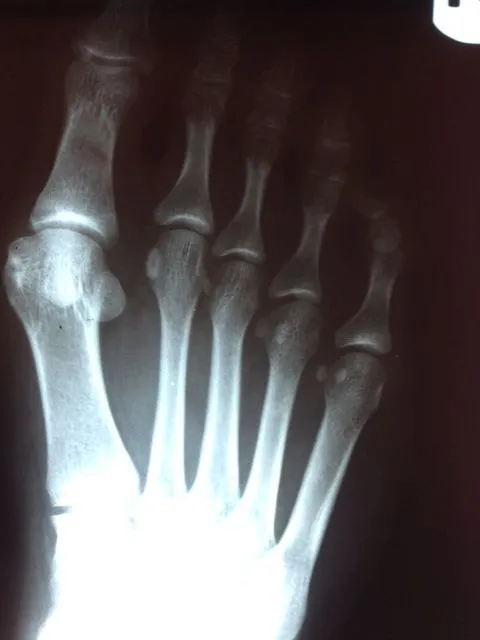

Before and immediately postop S/P bunionectomy

Before and 6 months status post bunionectomy.